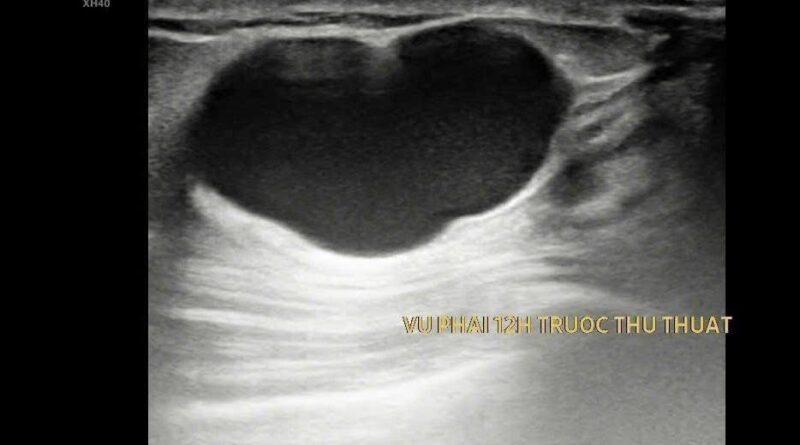

Điều trị diệt nang vú bằng các phương pháp can thiệp tối thiểu như tiêm cồn hoặc các chất gây xơ hóa sau chọc hút nang là phương pháp ít xâm lấn và tỷ lệ tái phát thấp.

Hiện bệnh viện Sản Nhi Ninh Bình đã thực hiện phương pháp điều trị tiêm xơ nang tuyến vú dưới hướng dẫn siêu âm, thực hiện nhanh chóng, thuận tiện ngay tại khoa Chẩn đoán hình ảnh. Giúp bệnh nhân điều trị hiệu quả, tránh tái phát, không cần vào viện và theo dõi tại nhà dưới sự hướng dẫn, dặn dò kĩ càng của bác sỹ điều trị trực tiếp.